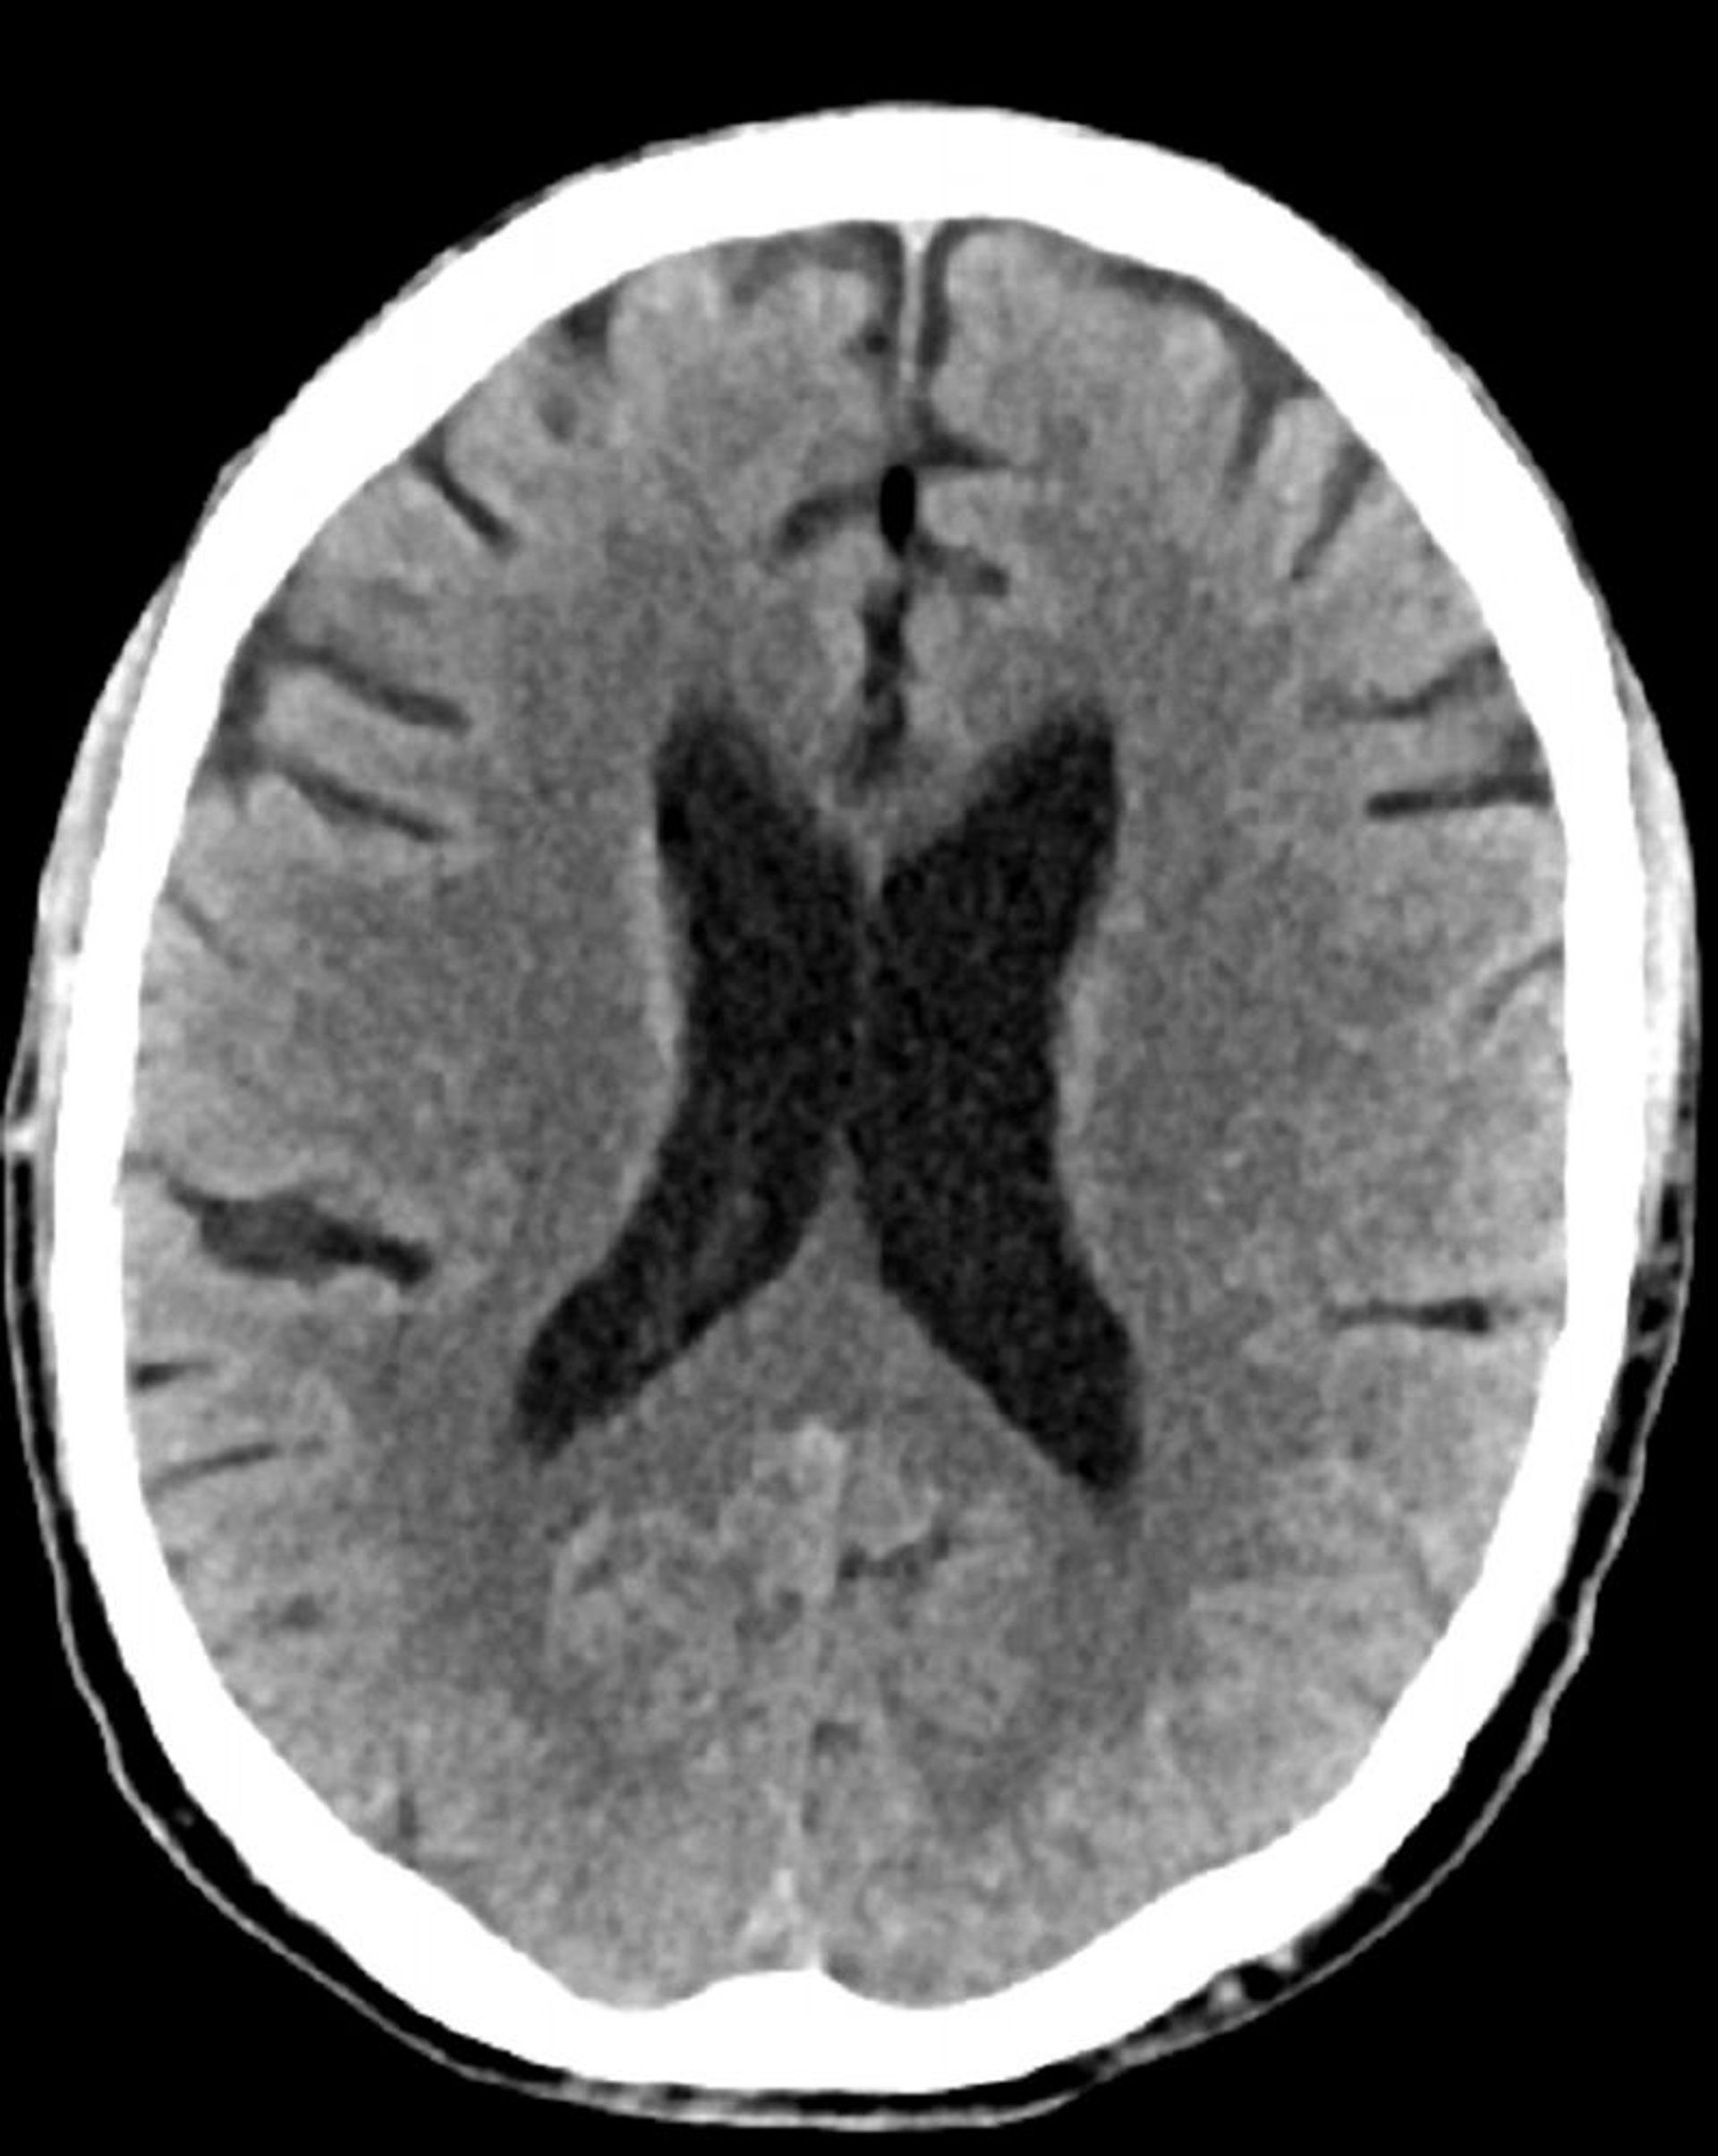

正常な頭部CT(成人,74歳)―スライド4

これは74歳成人の正常な頭部CT画像である。30歳の正常な頭部CT画像と比較すると,脳室および脳溝がより大きくなっている。これらの所見はこの年齢層では正常である。